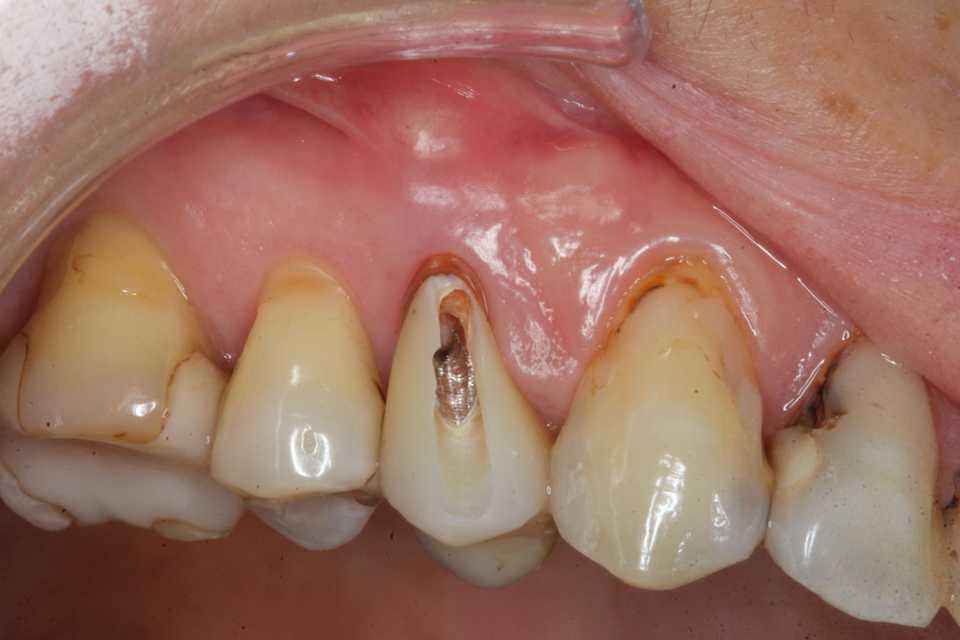

40代女性、右上4、Per+GAPerというのは根管治療後に根管内に感染を起こしている状態でGAとは炎症が根管の外に波及している状態。この方は10年程前に神経を取って被せたということでしたが、2、3年前GAができて別の歯医者に行ったら切って膿を出してもらったら治ったということでしたが、根管に細菌が感染している以上細菌が消えたりしないので、何度も再発します。今回は切開というよりは根管内部に3MIX+α-TCPを入れて根管内部を消毒殺菌しようというコンセプト。内部のポストも根管充填材も完全に除去する必要はない。根管充填材が見えるところまで穴を開けて薬剤を入れ、CRで蓋をするだけでよい。信じられないだろうが、これだけで治る。もし再発するようなら、冠のどこかに隙間があり、そこから細菌が出たり入ったりしているわけだから、冠もポストも除去して隙間を塞ぐ必要がある。多分従来の根幹治療しか知らない歯科医師は何が起こっているのか分からないと思うが、根管治療の真実が分かれば理解できないことはないと思う。一般に思われてる根管治療というのは理想からは程遠いものだということだ。冠にもポストにも根管充填材にも隙間だらけで細菌がその隙間から出入りしているのが現実だ。

僕が使っているボンディング材は​ こちら ​。α-TCPの50%クエン酸練り(硬化する)。

この上からCRダイレクトボンディングでカバーする。​ 3MIX+α-TCP

では時系列でどうぞ